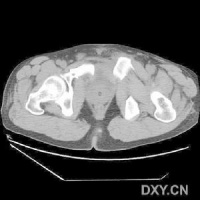

放射学检查[编辑 | 编辑源代码]

CT检查对骨盆骨折虽不属常规但它可在多个平面上清晰显示骶髂关节及其周围骨折或髋臼骨折的移位情况,因此凡涉及后环和髋臼的骨折应行CT检查骨盆三维重建CT或螺旋CT检查更能从整体显示骨盆损伤后的全貌,对指导骨折治疗颇有助益但应铭记对血流动力学鵻不稳定和多发伤患者,后前位全骨盆X线片是最基本和最重要鵻的放射学检查不要在拍摄特殊X线片上花费时间,更为重要的是尽快复苏。